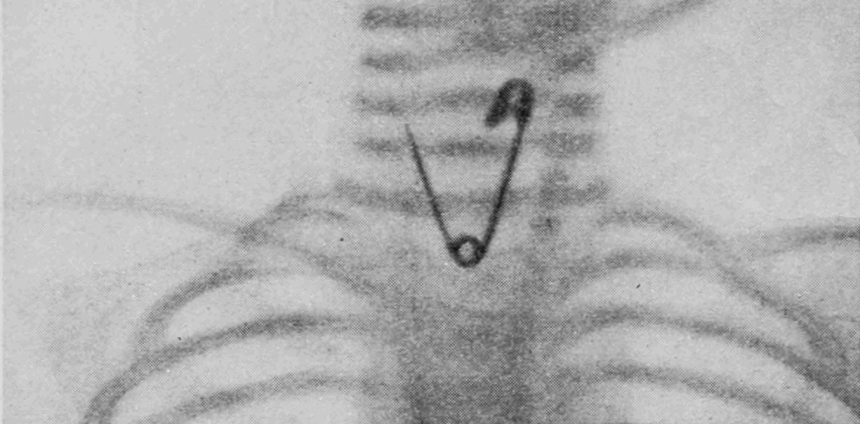

Já parou para pensar nas pessoas que têm objetos metálicos perdidos dentro do corpo? Segundo alertas médicos, moedas e baterias estão entre os itens mais ingeridos por crianças pequenas. Na maioria dos casos, é possível resolver o problema no consultório por meio de uma endoscopia – exame que usa um tubo com câmera para visualizar e retirar o objeto do esôfago ou estômago. Mas, quando o item passa desse ponto, a retirada fica muito mais complexa.

Os métodos tradicionalmente usados para localizar esse tipo de objeto em organismos são os exames de raios X tradicionais, tomografias computadorizadas ou radioscopias. Mas, embora eles identifiquem a região geral onde o material está, não têm resolução espacial para indicar a posição e profundidade exatas. Além disso, não há referências anatômicas viáveis, pois os objetos em geral estão alojados em tecidos moles, transparentes aos raios X. Uma desvantagem adicional é que expõem pacientes e equipe médica à radiação.